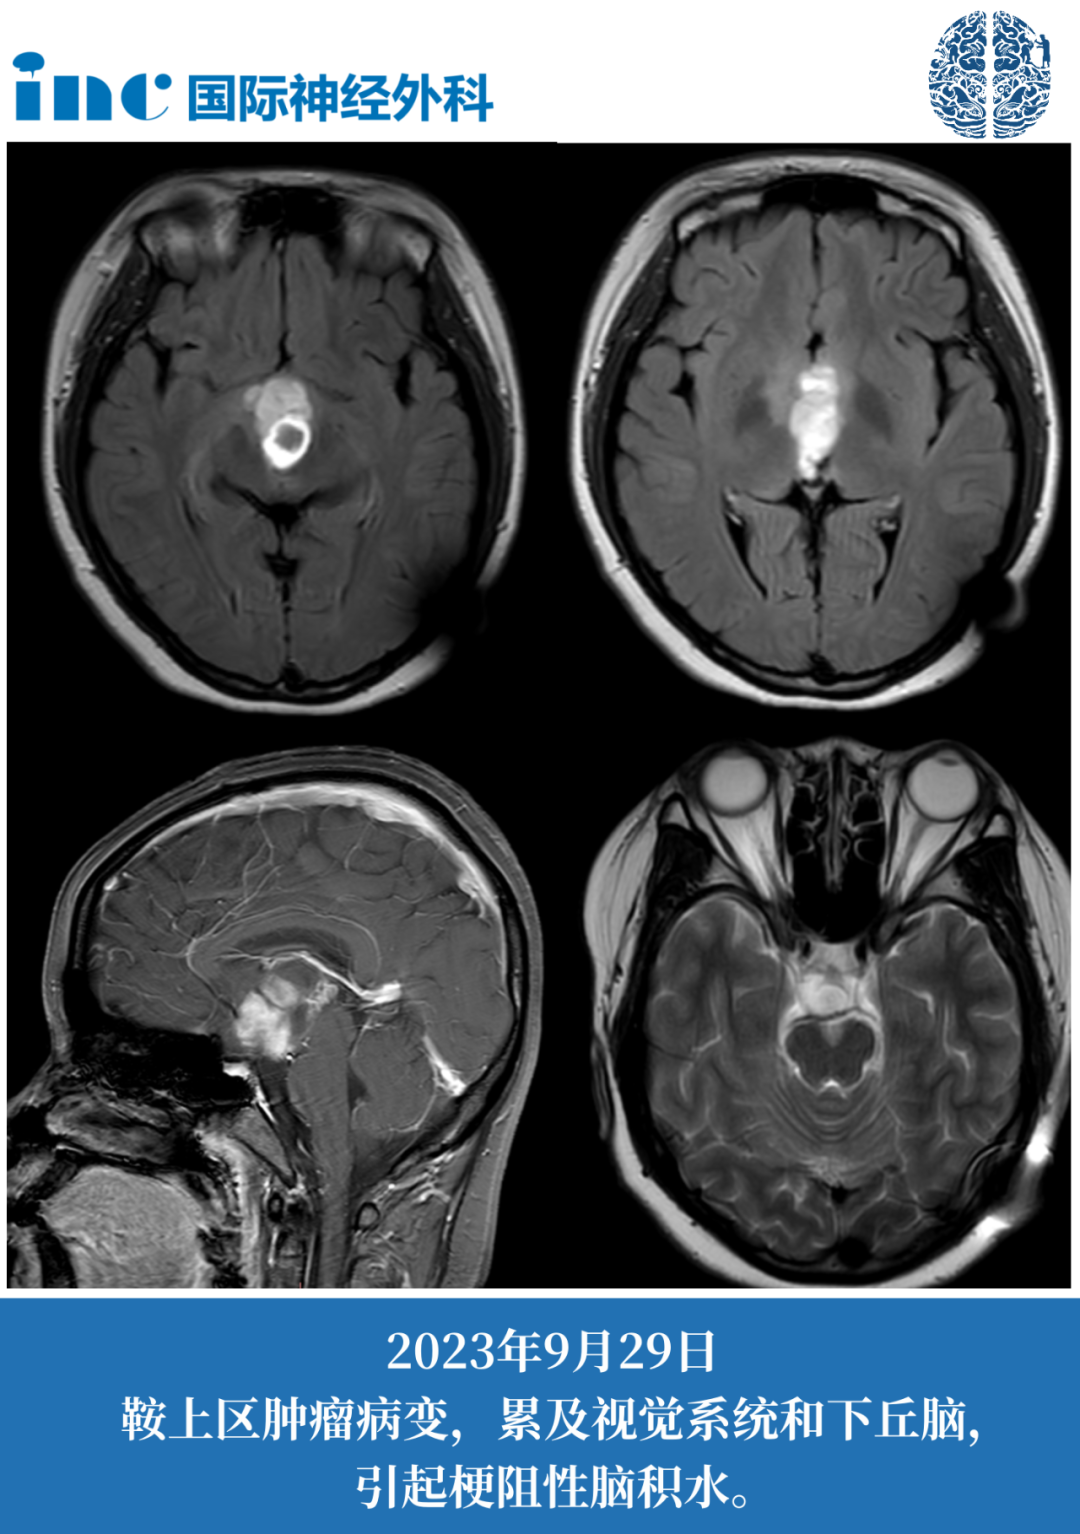

2023年5月,妙妙突然出现剧烈头痛症状,伴随呕吐临床表现。在当地医院进行颅脑CT检查后提示存在明显的脑积水情况。由于脑积水的临床表现较为严重,医生需要为妙妙实施排脑脊液的外科手术治疗方案。

进一步复查检查发现肿瘤组织具有很明显的占位效应表现,已经危及视神经及视交叉的临床功能(两者已经被肿瘤组织所累及),存在明确的外科手术临床指征。

术后第2天普通病房查房:妙妙临床意识状态表现清醒,能够正常打招呼交流。术后第4天普通病房查房:妙妙可以下地进行独立行走活动,临床状态表现逐渐好转恢复,巴教授专业告知术后核磁检查结果很好,肿瘤组织已经实现临床完全切除目标。